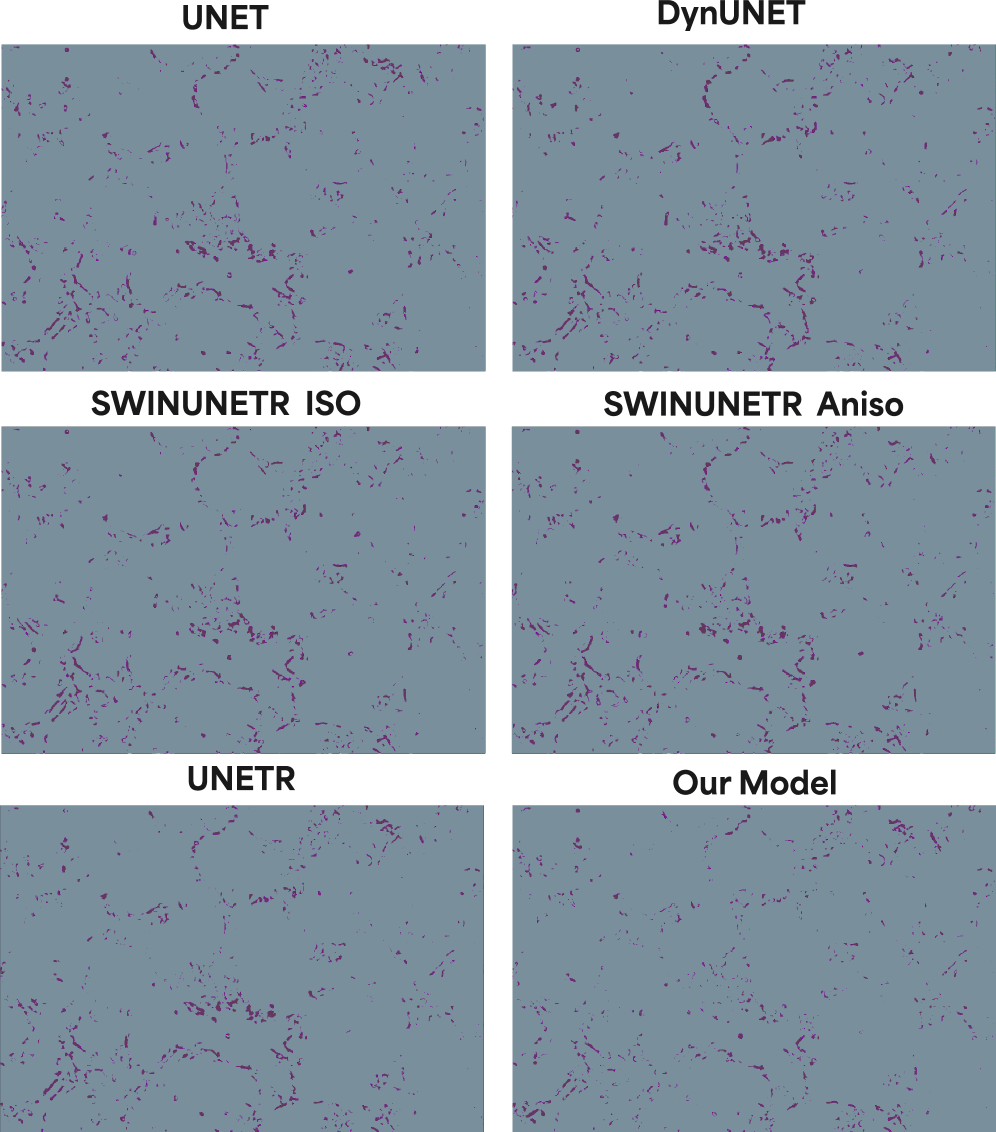

4.2 Mitochondria

We next evaluated our model on mitochondria, which we selected as an ideal intermediate validation target. This organelle poses a distinct challenge: its refractive index is significantly lower than that of nucleoli, resulting in a low-contrast signal, yet its tubular structures remain resolvable (i.e., above the diffraction limit).

Our model demonstrates high fidelity in this low-signal regime. It not only predicts the 3D location of the mitochondrial network—with high consistency at peripheral z-slices (top and bottom of the cell)—but also accurately resolves the orientation of individual tubules in sparse regions. This ability to capture fine-grained orientation from a convolved, low-contrast input strongly suggests the model is implicitly learning to invert the optical path and perform an effective deconvolution of the bright-field point spread function (PSF).

Architectural Benchmarks

We chose the number of parameters for each model based on empirical testing to make the comparison between our four billion parameter model as fair as possible. These parameter counts were the most effective for learning the mitochondria structure, and we found that anything below or above these either degraded the performance or added more compute with little to no gain in segmentation accuracy. More precisely, we noticed that for the base UNET, adding more parameters produced more blobby structures and focus shifted more on overall shape, while too few parameters learned the inherent brightfield noise. The transformer-based models produced reasonable results all within the range. One of our core innovations is seen in Table 1, wherein our model despite being four billion parameters only occupies an inference memory footprint of 26GB, which is several scales less than the dense networks. All models were tested with a batch size of one, and all image and patch sizes were the same across all models.

| Metric | UNet | DynUNet | UNETR | SwinUNETR | Ours (No MoE) | Ours |

|---|---|---|---|---|---|---|

| Params | 438M | 91M | 211M | 248M | 171M | 4B |

| IMF | 20GB | 51GB | 81GB | 110GB | 24GB | 26GB |

| Hausdorff | 57.94 | 57.94 | 50.98 | 53.41 | 56.55 | 46.08 |

| IoU | 0.396 | 0.319 | 0.368 | 0.362 | 0.287 | 0.42 |

| Precision | 0.496 | 0.369 | 0.452 | 0.452 | 0.341 | 0.532 |

| HD95 | 29.53 | 29.54 | 13.84 | 18.72 | 24.01 | 9.86 |

| Dice Score | 0.566 | 0.482 | 0.538 | 0.531 | 0.445 | 0.591 |

| Rel. Volume Error | 37.11 | 95.92 | 51.92 | 47.13 | 95.11 | 25.52 |

| Avg Surface Dist (mm) | 6.155 | 6.154 | 2.083 | 2.599 | 3.694 | 1.598 |

| Component Count Error | 694.61 | 677.06 | 1233.44 | 697.41 | 2898.16 | 1577.92 |